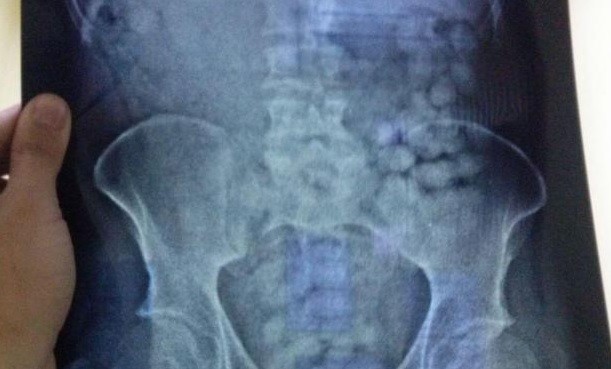

Una radiografía mostró en la zona abdominal la presencia de objetos extraños en formas de cápsulas. El hombre fue intervenido quirúrgicamente en el Hospital Maciel y se contabilizaron 135 cápsulas de cocaína con un peso total de 1.093 gramos de droga de alta calidad.